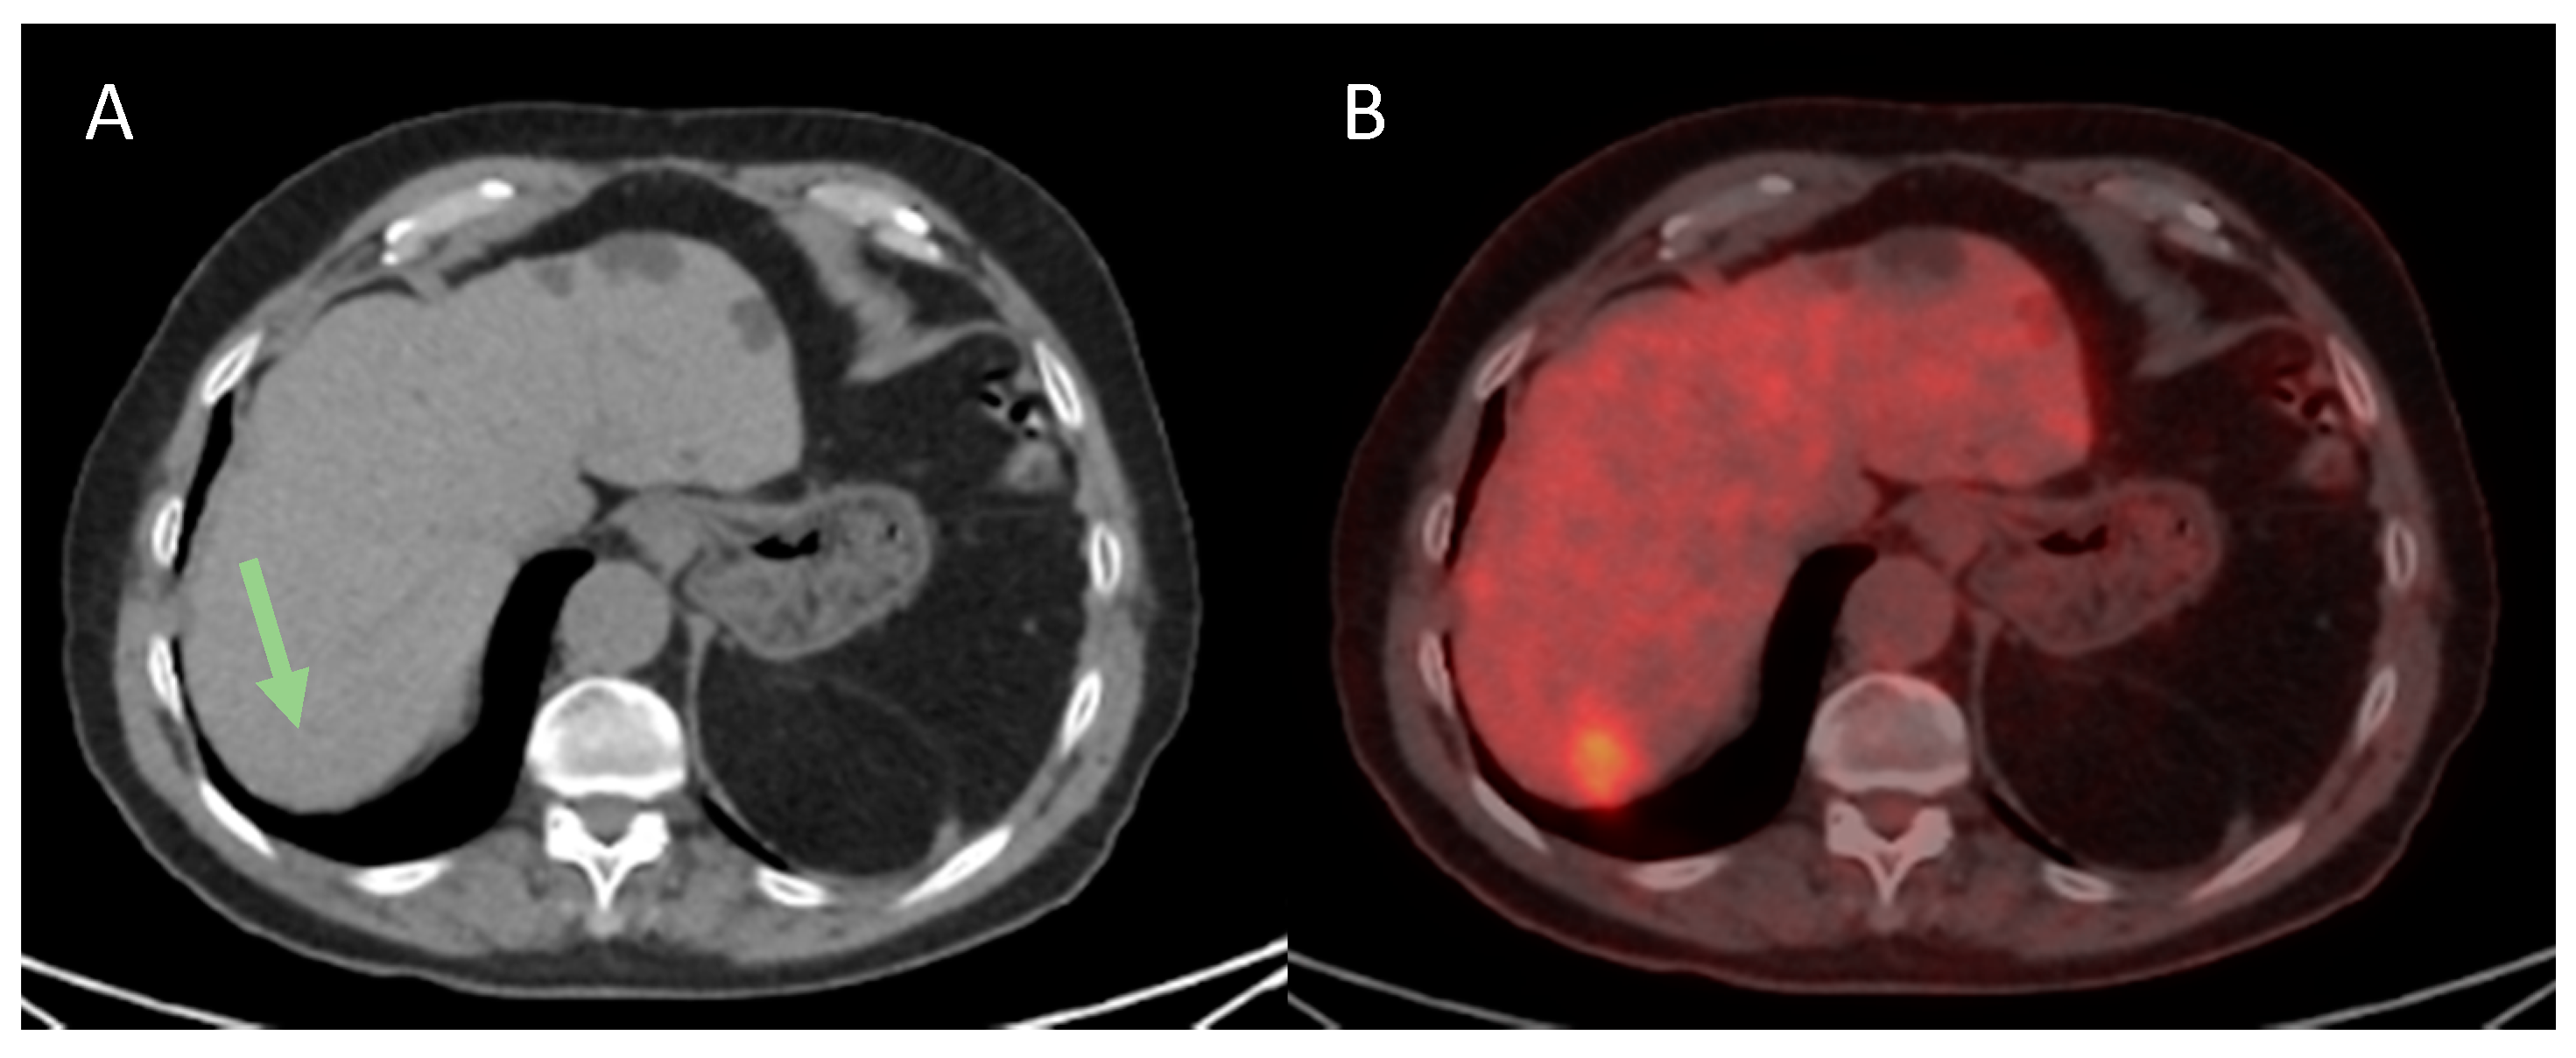

3.3.1. Presence of MVI